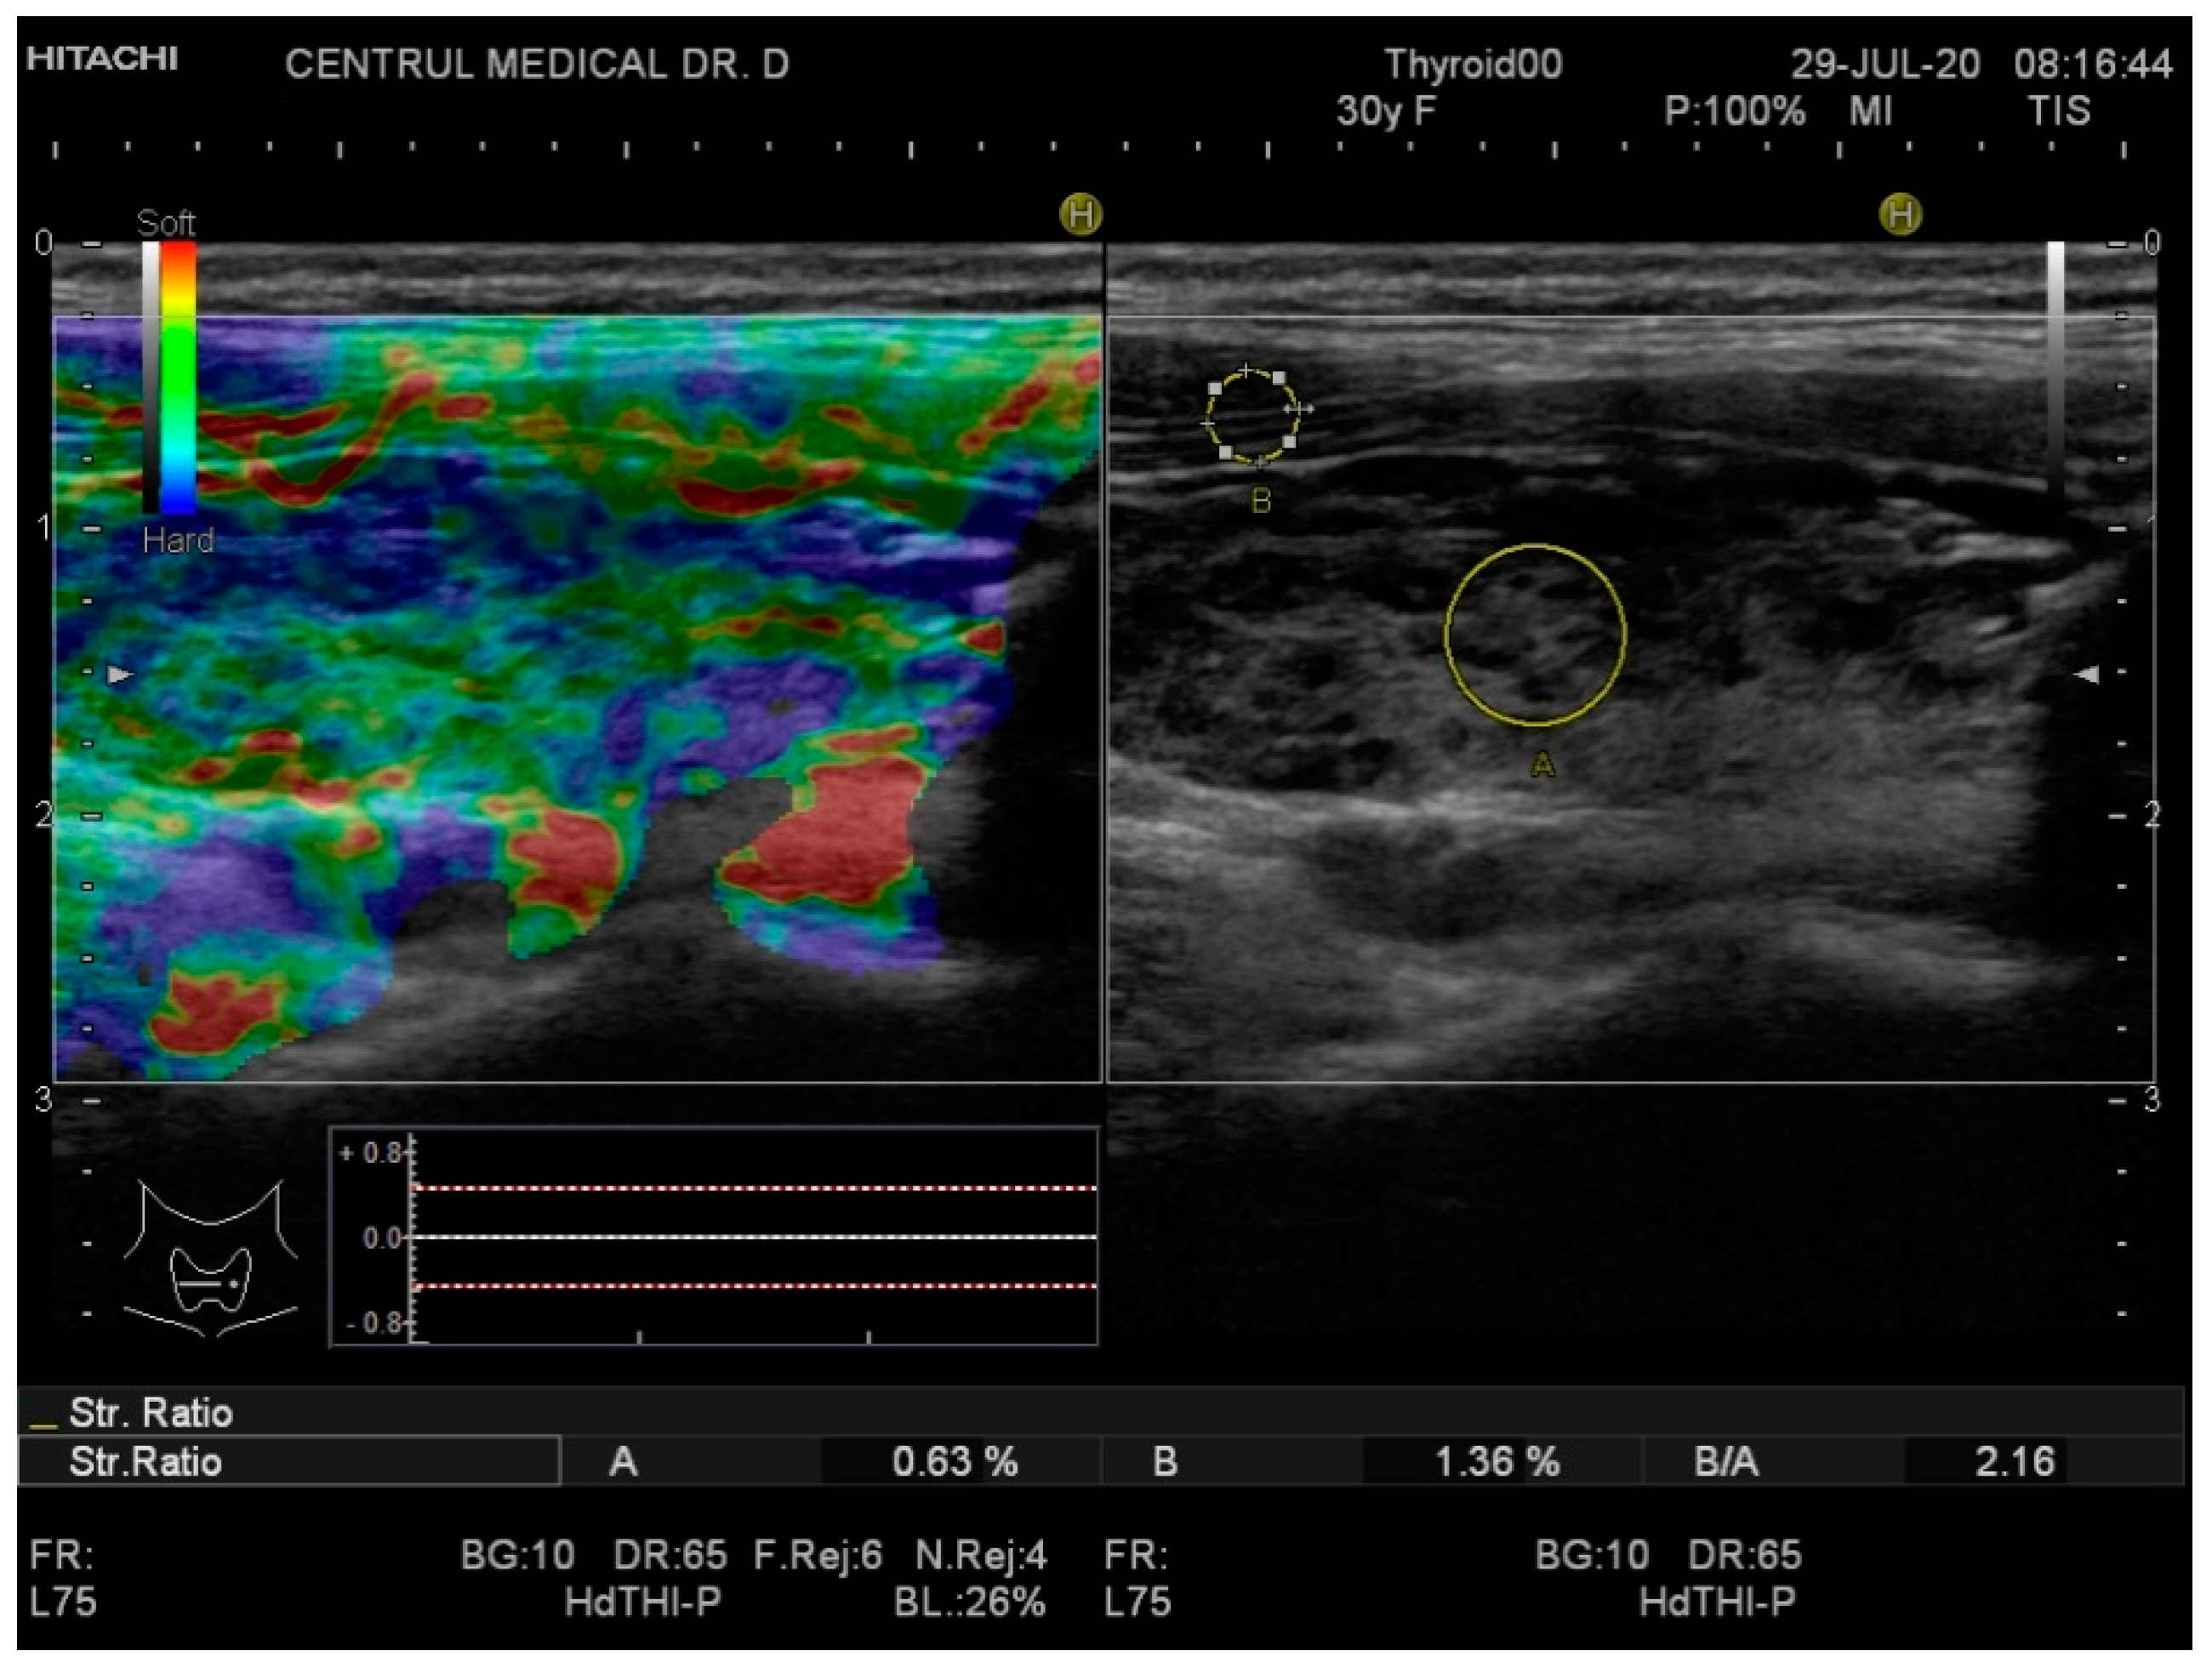

Real-time elastography was performed after conventional US during the same visit. The stiffness measurements were collected in the same session as the grey-scale US evaluation. The probe was placed perpendicularly to the skin and repetitive, light compression was applied avoiding lateral movement. All images were obtained in the longitudinal plane. A blue-green-red color map was displayed with blue indicating no strain (high stiffness), green indicating intermediate stiffness and red representing soft tissue. In order to calculate the strain ratio (SR), two regions of interest (ROI) were placed consequently. The first one, ROI A, was the thyroid tissue while the second one, ROI B, was the sternocleidomastoid muscle in front of the ipsilateral thyroid parenchyma. Figure 1 and Figure 2 below illustrate the SE image and calculation of the SR in normal thyroid tissue and, respectively, in a patient with CAT. Five consecutive measurements were made for each lobe and the mean value was considered in the final evaluation. The SR was calculated and displayed automatically for each lobe.

Figure 2.

Strain elastography (left) and conventional US (right) of a patient diagnosed with chronic autoimmune thyroiditis (CAT)—right thyroid lobe. The yellow circle A is the local ROI on the thyroid tissue; the yellow circle B is the local ROI on the adjacent sternocleidomastoid muscle. SR = 2.16.